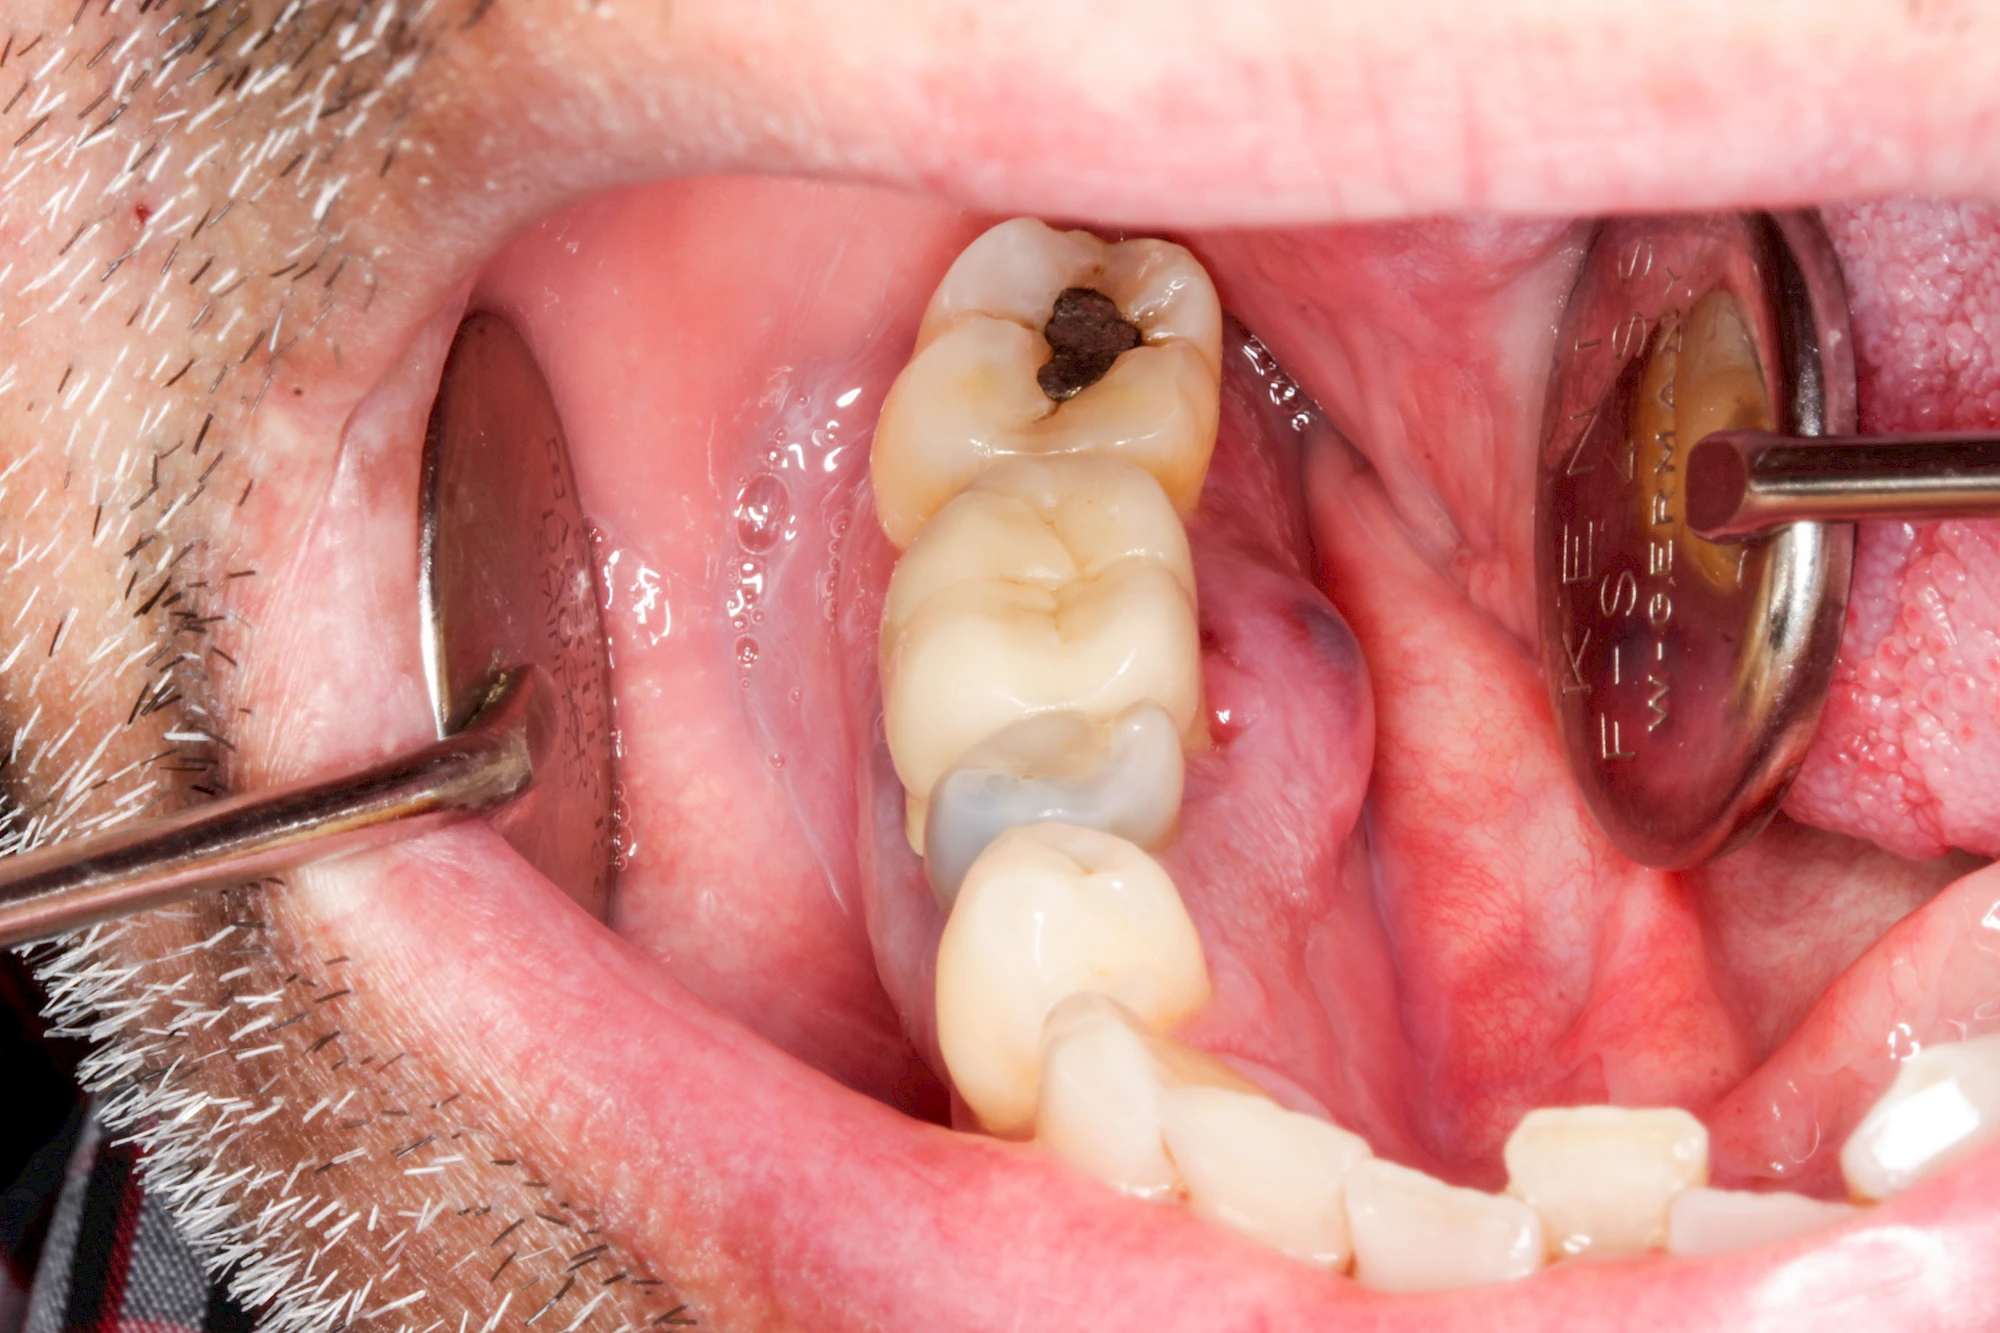

Ist zunächst nur das Zahnfleisch von der Entzündung betroffen, spricht man von Gingivitis. Später, wenn auch der Knochen um die Zähne herum entzündet ist, spricht man von einer Parodontitis. Bei der Parodontitis wird der Knochen nach und nach abgebaut und das Zahnfleisch zieht sich zurück. Die Zahnhälse und Zahnwurzeloberflächen liegen mehr und mehr frei. Die Zähne werden zunehmend lockerer und fallen schließlich aus.

Sonderform: Fistel

Bei einer Fistel hat sich meist eine Entzündung (manchmal auch Erreger selbst) z. B. aufgrund von Karies oder aufgrund eines Unfalls über den Zahnnerv und die Wurzelspitze (Apex) in den umliegenden Knochen ausgebreitet (apikale Parodontitis) und schnell einen Weg durch den umgebenden Knochen und die aufliegende Schleimhaut in die Mundhöhle gebahnt.

Fisteln sind in der Regel nicht schmerzhaft und fallen häufig als kleine Öffnung weiter entfernt vom Zahnfleisch nahe der Umschlagfalte auf. Aus der Fistelöffnung entleert sich spontan gelbliches Sekret (Eiter) oder es lässt sich mit dem Finger ausstreichen. Manchmal beschreiben die betroffenen Menschen immer wieder einen komischen Geschmack im Mund.

Im fortgeschrittenen Stadium kann die Schleimhaut sich weiter zurückgezogen haben und die Wurzelspitze sichtbar sein. In der Regel treten bei Fisteln keine Schwellungen auf, weil sich die Entzündung nicht im Gewebe ausbreitet.